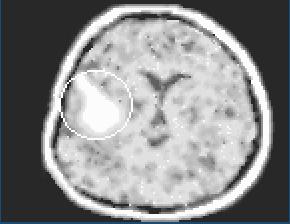

Biela šrvrna znázorňuje aneurizmu, výduť. Operácia je nevyhnutná.